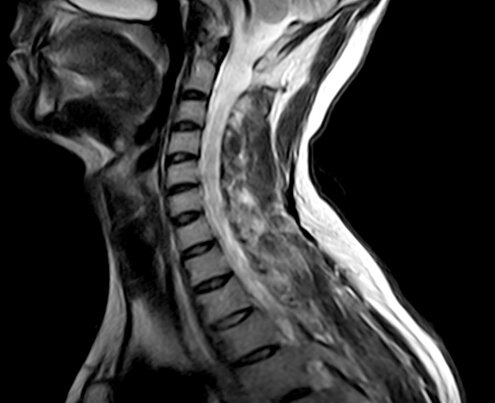

МРТ с успехом используется в медицине с 70-х годов прошлого века с целью максимально точной визуализации состояния как внутренних органов, так и всех хрящевых, костных и мягких тканей организма. Этот метод общепризнан врачами, хорошо апробирован и известен своей безошибочностью и информативностью. Принцип работы томографа строится на эффекте ядерного магнитного резонанса. Благодаря  диагностическим способностям электромагнитных волн специалистам удаётся получить очень детальные изображения позвонков, мягких тканей шеи, межпозвоночных дисков, нервных окончаний, сосудов, спинного мозга и желез. Особенно активно и успешно томография используется в обследовании пациентов с патологиями нервной сети, спинного мозга, сосудов и опорно-двигательного аппарата.

МРТ шейного отдела позвоночника

МРТ шейного отдела позвоночника нацелена на сканирование хрящей, пульпозного ядра, дисков шейных позвонков, дужков позвонков, возможных деформаций позвоночного канала, аномалий циркуляции спинномозговой жидкости, защемлений нервных окончаний и воспалений прилегающих тканей мышц и сухожилий. Посредством данного вида томографии шеи неврологи безошибочно диагностируют такие заболевания, как: